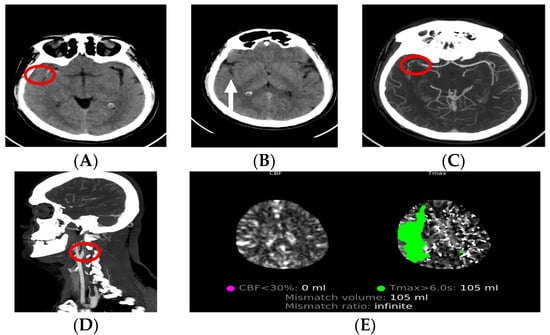

3.2. CT Angiography

3.3. CT Perfusion

3.4. MRI in Ischemic Stroke